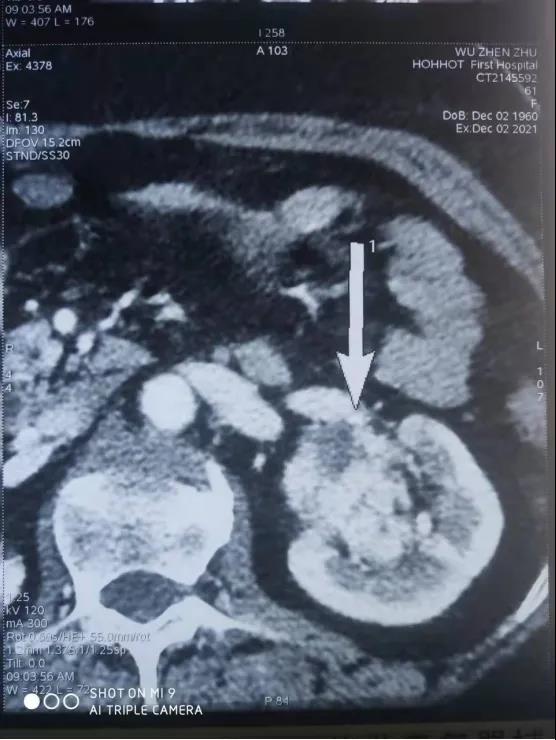

患者,女性,61岁,因体检发现左肾肿物一周收入院,入院后行全腹部增强CT检查回报:左肾下极肿瘤。大小48*47mmhg,肿瘤分期:T1bM0N0,肿瘤位于肾实质深部,上极紧贴肾门,各期影像显示患肾血供复杂:包括肾动脉、副肾动脉各一支。

肾静脉两支

变异血管分布如下:

第四腰椎椎前血管发出的侧支动脉一支

穿过后腹膜入肾上极变异动脉一支(来源于脾动脉)

肿瘤回流静脉一支(内有癌栓)